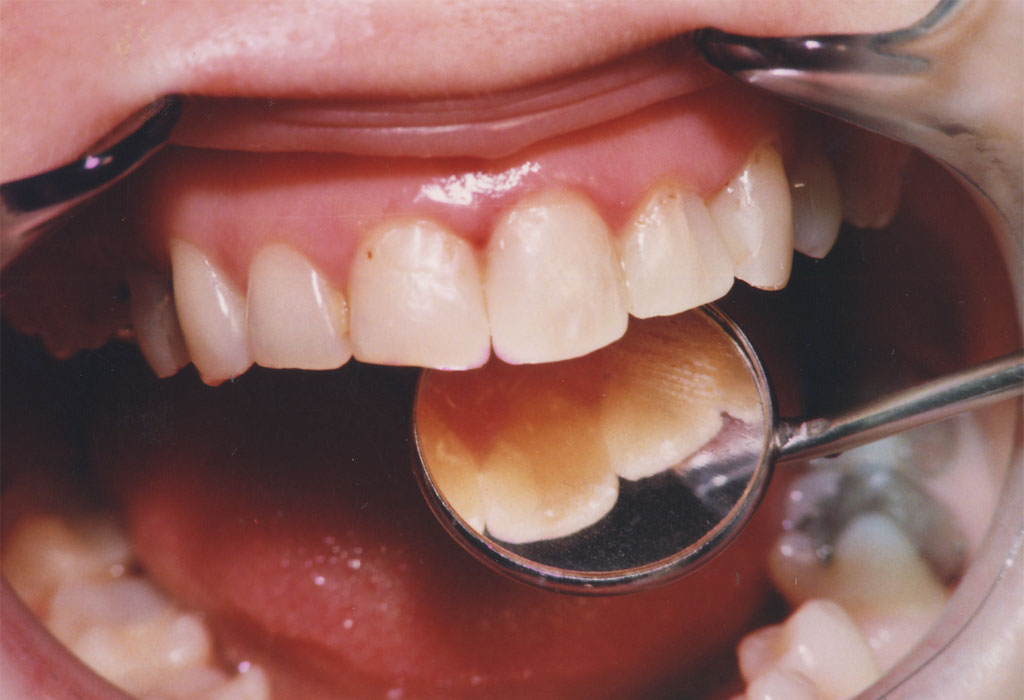

Upotreba savremenih nanohibridnih kompozita renomiranih svetskih proizvođača omugućuje izradu plombi vrhuskog kvaltiteta i estetike.

Rekonstrukcijom zuba po boji, obliku i veličini plombe izgledaju potpuno prirodno i traju dugi niz godina.